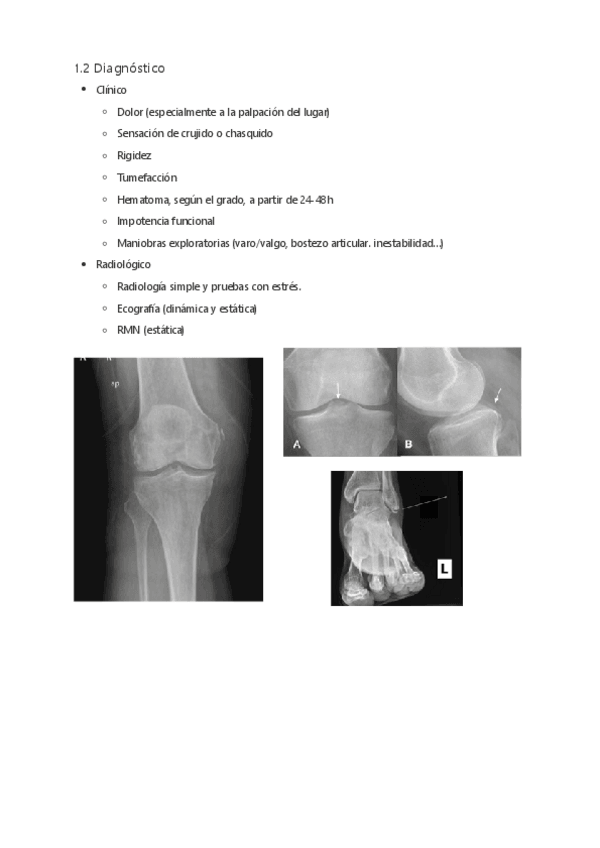

He publicado nuevos apuntes de 2º Afecciones médico-quirúrgicas I: Tema-12-Patologia-articular-traumatica.pdf